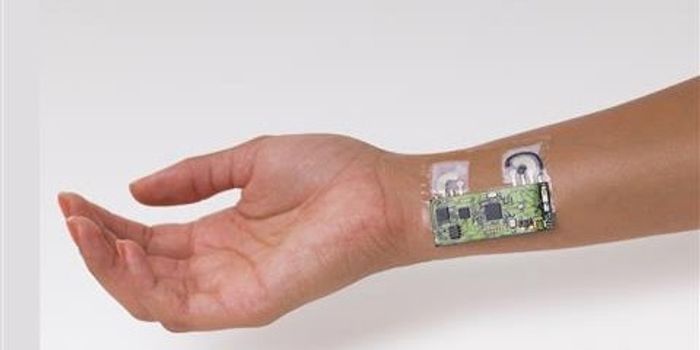

NOV 28, 2017VideosWhile fitness trackers like FitBits seem to be everywhere, a new device to monitor health is being developed, and it aim ...